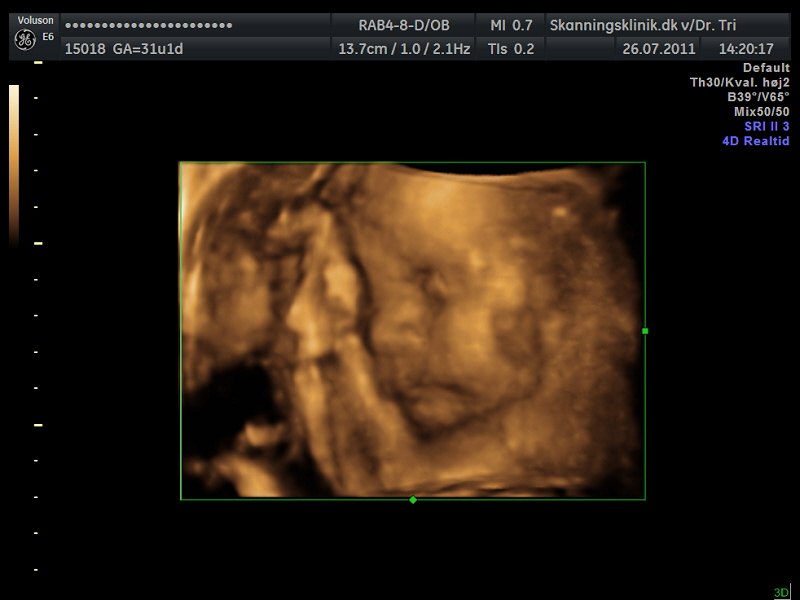

Så blev det tid til en lille 3D/4D-scanning af bettemanden!!

Jeg er i dag 31+2 og var i eftermiddags til 3D/4D-scanning, på skanningsklinikken i Hvidovre, og sikke en oplevelse, helt sikkert alle pengene værd!!

Lillemanden var dog noget svær at få gode billeder af, da han havde skruet numsen ned i mit bækken og synes han skulle ligge med begge hænder og fødder direkte foran hans lille nuttede ansigt hehe.. Så mor her måtte op at hoppe flere gange og fik koldt vand og måtte have maven gennem-rystet flere gange, men alligevel var han nooget på tværs hehe.. Den lille bølle..

Men der kom dog til sidst nogle helt okay billeder ud af det!!

Og så liige lidt billeder, så I også kan se min fine guldklump...

Som I kan se er der lidt hånd og fod med på alle billederne, og på det sidste billede har bettemanden fat om foden med den ene hånd.. Lille hypermobile skid..